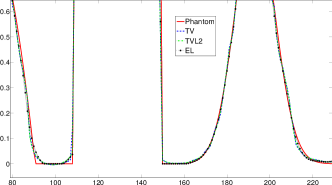

Reconstructed images are presented in Fig. 4. Since CGLS-TV- reconstruction might look more appealing than CGLS-EL we also show the surface representations of reconstructed images (see Fig. 5) and horizontal middle cross-sections (see Fig. 6).

One can notice that CGLS reconstruction is very noisy. CGLS-TV method better suppresses noise, however smooth features are strongly affected by the “staircasing” effect. CGLS-TV- method provides reconstruction with smoother features and CGLS-EL method resolves smooth features even better (e.g. cone-shaped parabola). Although CGLS-EL method performs very well for smooth objects one can notice the wave-like variations of intensity in the background and also at the top of the rectangle (see Fig. 6). This issue can be explained by the properties of our regularizer, in contrast to TV, our penalty does not seek the sparsest solution and does not penalize strongly (pushing to the constant value) a small intensity perturbations. The EL term tends to preserve all sharp edges while uniform noise is smoothed isotropically with the Laplacian. In Fig. 6 one can see that the CGLS-EL method provides better recovery of smooth features while slightly higher (compare to TV and TV-) perturbations visible in uniform areas (the top of the rectangle), however, the edges of the rectangle are defined sharper with the EL penalty.